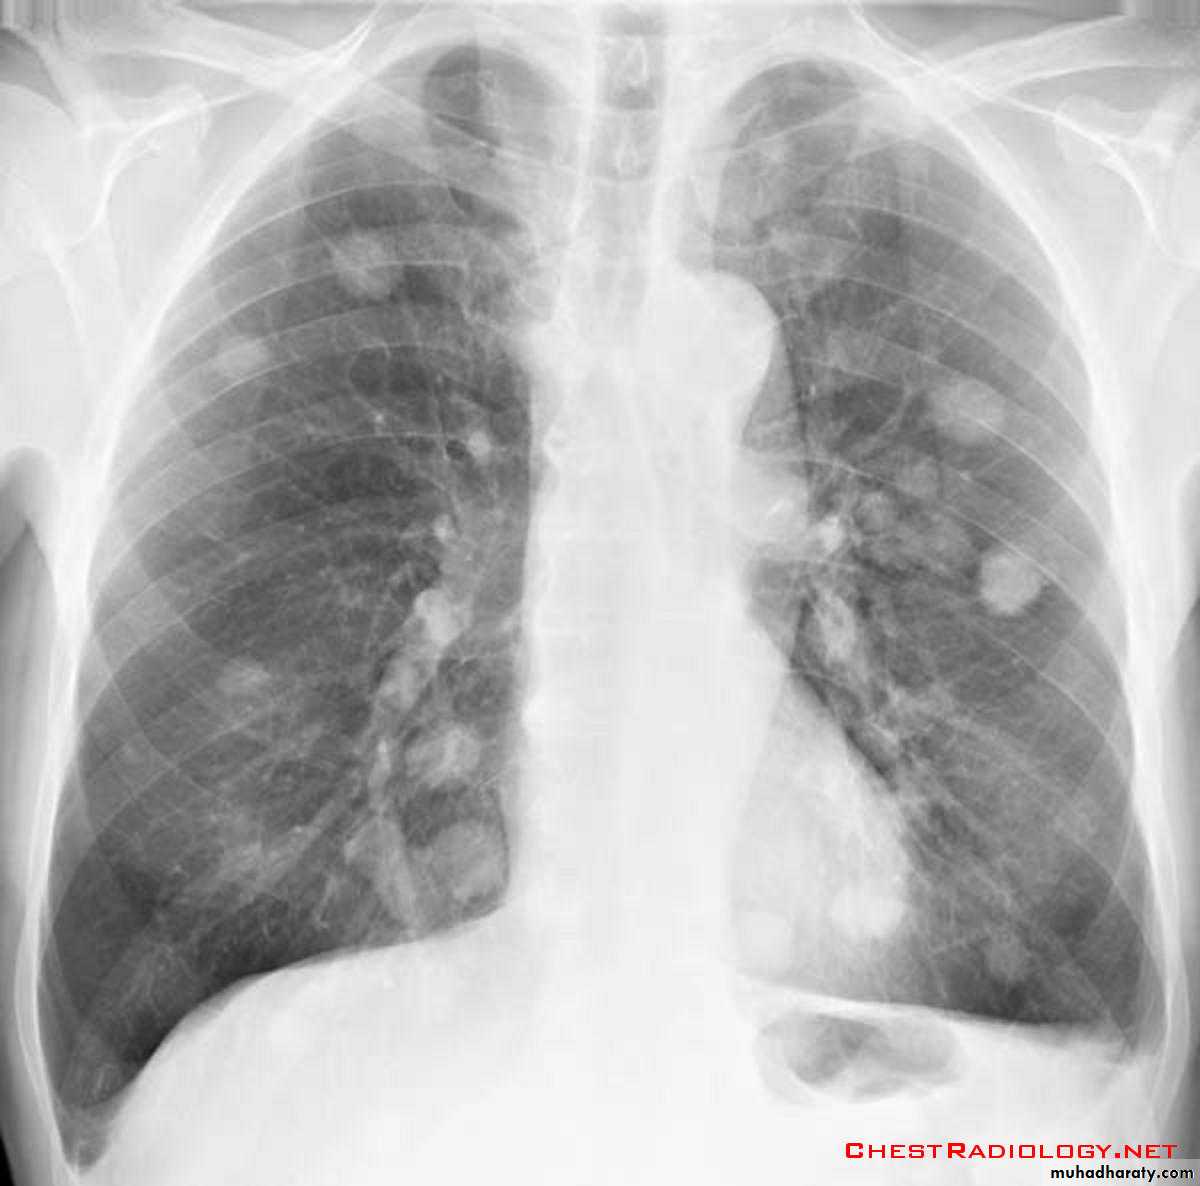

Pulmonary metastases are common and the result of metastatic spread to the lungs from a variety of tumors and can spread via blood or lymphatics.1.Cannonball metastases refer to large well circumscribed, round multiple opacities like cannonballs

2.lymphangitis carcinomatosis , is the term given to tumor spread through the lymphatics of the lung , and is most commonly seen secondary to adenocarcinoma Unfortunately up to a quarter of patients with subsequently established lymphangitic carcinomatosis have normal chest x-rays . When abnormal the most common finding is of a reticulonodular pattern, with thickening of the interlobular septae which may resemble Kerley B lines + /- pleural effusion .

3.innumerable small metastases (miliary pattern).